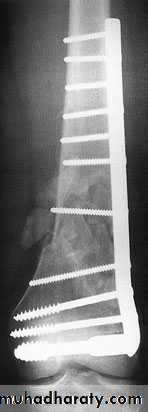

In old internal fixation is often preferable and the patient can get out of bed sooner (dynamic condylar screw and plate) .

dynamic condylar screw and plate

Supracondylar fracture with its fixation by L – plate and screws